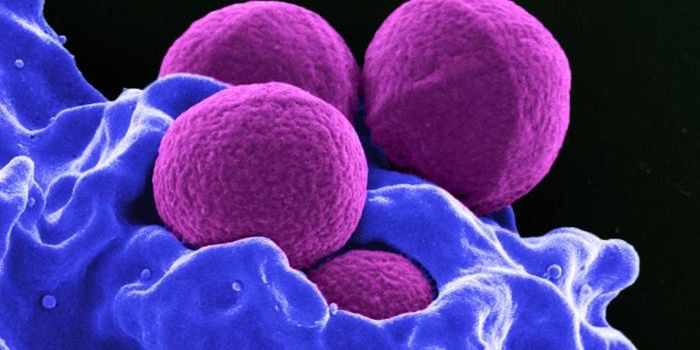

AUG 20, 2016Clinical & Molecular DXCan the staph superbug, also known as MRSA, be brought down by salt? Scientists finally expose a key weakness in these b ...

MAR 11, 2015MicrobiologyHouseholds can serve as a reservoir for transmitting methicillin-resistant Staphylococcus aureus (MRSA), according to a ...